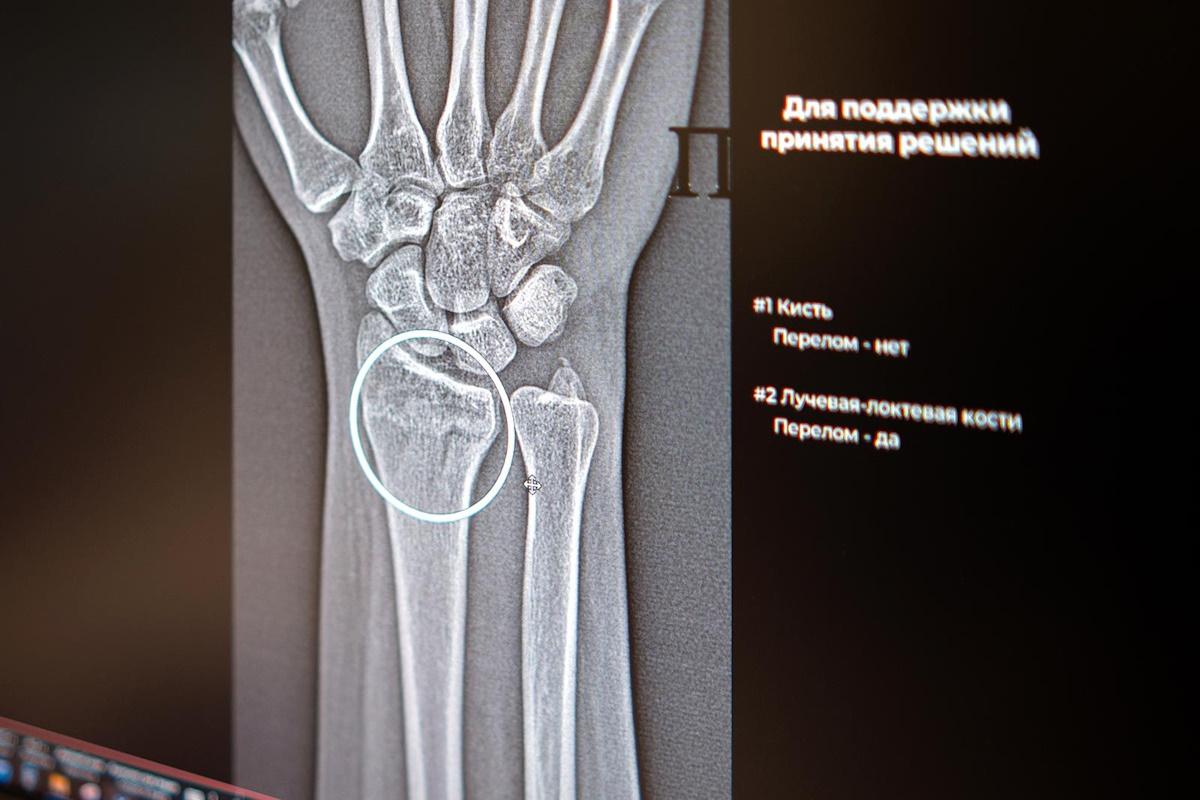

В Москве начали работу два новых сервиса на базе ИИ, предназначенных для высокоточной идентификации множественных переломов в области голеностопа и запястья. Теперь общее количество разнообразных, с точки зрения функциональности, ИИ-инструментов для специалистов в области рентгенологии достигло 60.

Цифровые технологии более пяти лет оказывают поддержку московским рентгенологам, преимущественно в процессе анализа медицинских изображений. Недавно были введены в эксплуатацию два новых ИИ-сервиса, которые помогают выявлять травматические повреждения костей в голеностопном и лучезапястном суставах – одних из наиболее функциональных и одновременно подверженных травмам областей. Алгоритмы автоматически выделят поврежденные зоны и произведут необходимые замеры, даже если на снимке визуализируются признаки нескольких переломов одновременно.

ИИ-технологии в области лучевой диагностики анализируют изображения, опираясь на множество параметров, помогают в проведении требуемых расчетов и ускоряют процесс описания снимков. Они способны обнаруживать даже незначительные трещины и указывать врачу на наличие множественных переломов в одной и той же области. Точная диагностика напрямую влияет на выбор оптимальной стратегии лечения, сообщили в столичном департаменте здравоохранения.